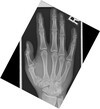

54

What pathology is shown here?

Boxers #

What pathology is seen here?

Bennetts fracture